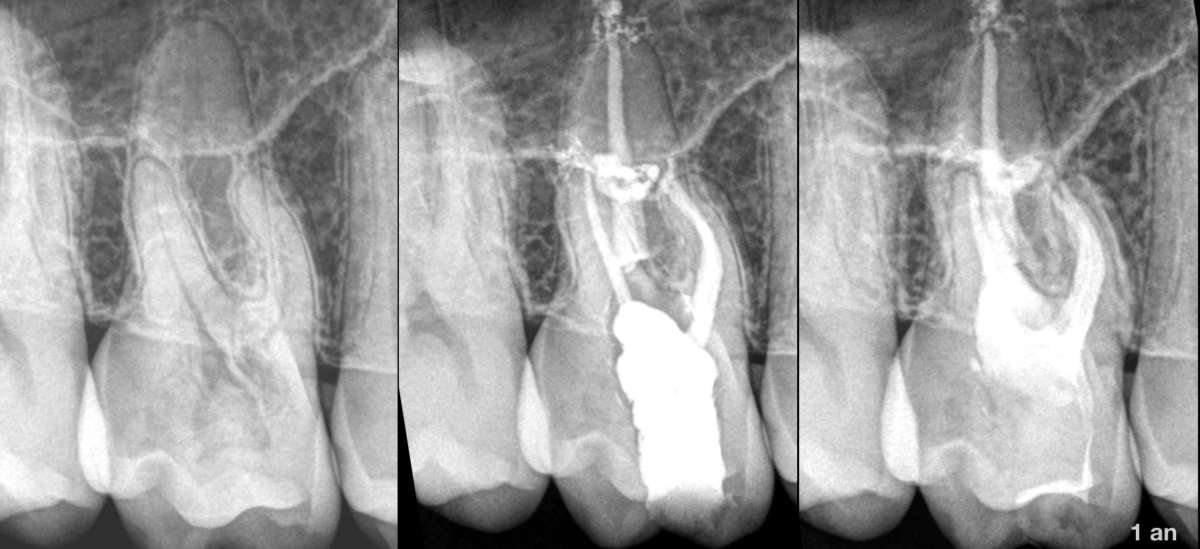

🔍 𝐏𝐮𝐥𝐩𝐞 𝐧𝐨𝐫𝐦𝐚𝐥𝐞

✅ 𝐎𝐬 𝐩𝐞́𝐫𝐢–𝐚𝐩𝐢𝐜𝐚𝐥 𝐧𝐨𝐫𝐦𝐚𝐥

⚠️ 𝐑𝐞́𝐬𝐨𝐫𝐩𝐭𝐢𝐨𝐧 𝐫𝐚𝐝𝐢𝐜𝐮𝐥𝐚𝐢𝐫𝐞 𝐞𝐱𝐭𝐞𝐫𝐧𝐞 𝐢𝐧𝐟𝐥𝐚𝐦𝐦𝐚𝐭𝐨𝐢𝐫𝐞 à porte d’entrée cervicale.

🦷 𝐓𝐫𝐚𝐢𝐭𝐞𝐦𝐞𝐧𝐭 𝐜𝐚𝐧𝐚𝐥𝐚𝐢𝐫𝐞 + 𝐭𝐫𝐚𝐢𝐭𝐞𝐦𝐞𝐧𝐭 𝐝𝐞 𝐥𝐚 𝐫𝐞́𝐬𝐨𝐫𝐩𝐭𝐢𝐨𝐧 𝐩𝐚𝐫 𝐯𝐨𝐢𝐞 𝐢𝐧𝐭𝐞𝐫𝐧𝐞.